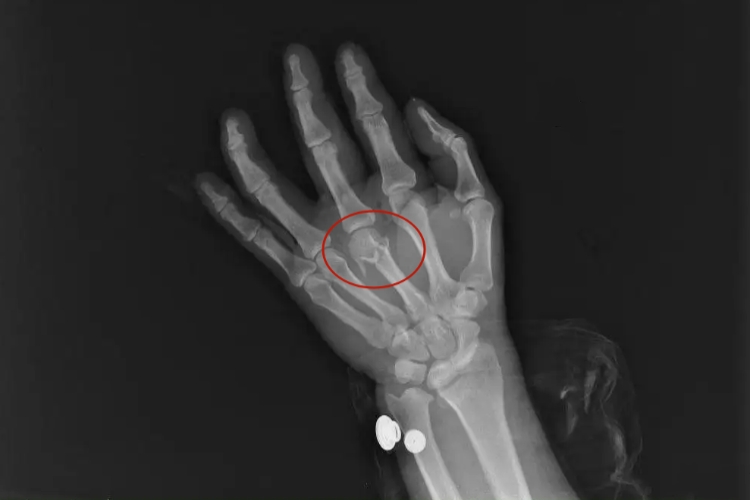

手掌粉碎性骨折通常指掌骨粉碎性骨折,可出现损伤部位的疼痛、肿胀、畸形等表现,可能是直接暴力或间接暴力引起,需及时治疗。

手掌粉碎性骨折患者可有局部肿胀、疼痛、压痛、畸形、异常活动、骨擦音、骨擦感、活动障碍、纵向叩击痛等表现。同时由于骨间肌、蚓状肌、屈指肌、伸指肌的牵拉,掌骨骨折患者的骨折端会向背侧成角。

手掌粉碎性骨折不稳定,多为开放性骨折,在适当清创后用克氏针固定4-5周。有明显重叠和旋转畸形患者,应进行切开复位。